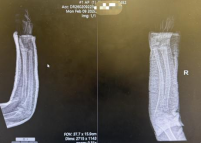

复位成功后,孩子原本扭曲变形的前臂也恢复了正常轮廓。团队为患儿采用超腕超肘石膏托进行外固定。这种特殊固定方式既能有效维持复位后的位置、防止再移位,又能通过精准塑形贴合前臂生理弧度,为骨折愈合提供稳定而舒适的环境。

复位后即刻复查的X线片正位片显示,桡骨与尺骨骨折端对位良好,侧方移位完全纠正;侧位片显示掌背侧成角畸形已有效矫正,力线接近正常。